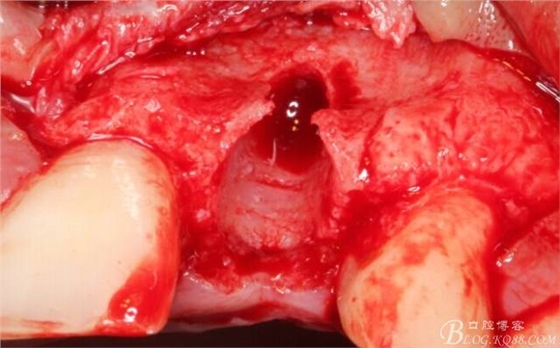

翻開后驚喜的發(fā)現(xiàn),術(shù)區(qū)成骨非常好,去除部分骨才暴露那顆長鈦釘。

取出影響種植入路的長鈦釘。